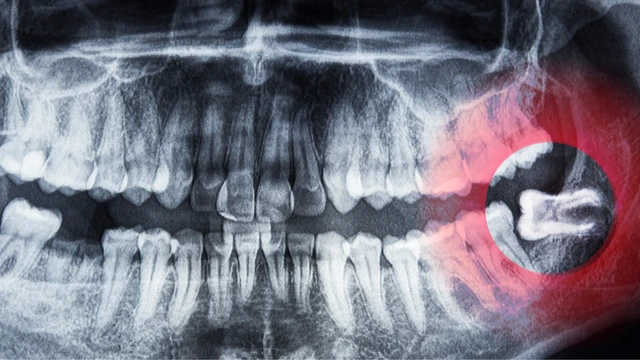

Lợi trùm răng cửa nếu không được điều trị sớm sẽ làm tăng khả năng mắc nhiều bệnh răng miệng, nguy hiểm hơn là nguy cơ nhiễm trùng lây lan đến vùng khoang đầu và cổ cùng, từ đó tăng ảnh hưởng đến đường thở và đe dọa trực tiếp đến sức khỏe.